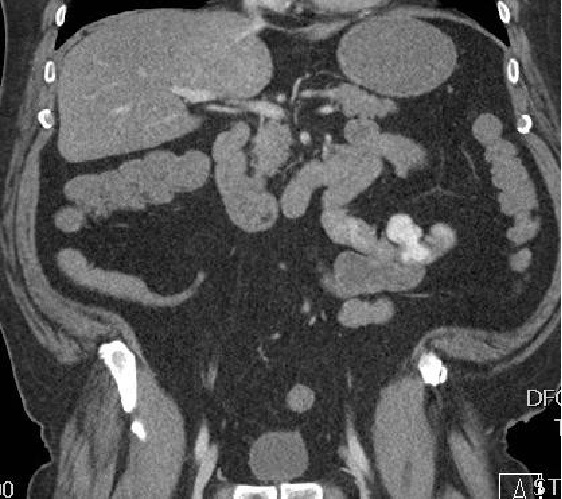

增强CT扫描

仍然不能确定具体出血血管 |